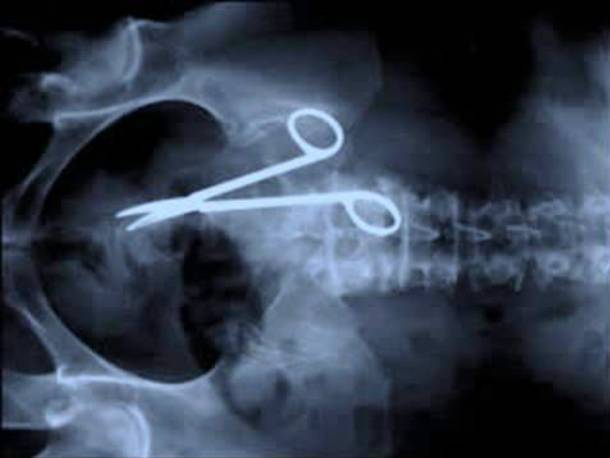

The rights of a patient have improved over the years and with this is the growing knowledge about what your rights are when something does go wrong. If you have had care or treatment that is inadequate, delays that are outwith the waiting times targets (currently 18 weeks for referral and 12 weeks for a new outpatient appointments) you are entitled to make a complaint and receive a full answer. Beyond an initial complaint, you also have the option of pursing a claim if your care amounted to negligence, which damaged your health (misdiagnosis or mistakes in surgery for example) and would not have occurred otherwise.

Medical Negligence

In Scotland a claimant has 3 years from the date that they knew, or should have reasonably known, that negligence occurred and caused injury. In order to be successful, it must be established that the course adopted by the medical practitioner was a course that no other medical practitioner in that position would have adopted, when acting with ordinary care.